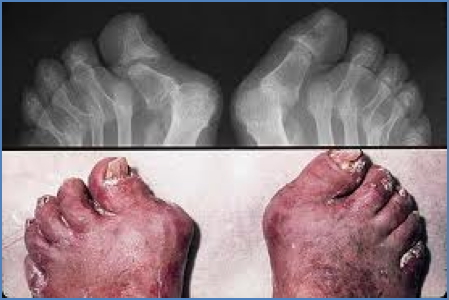

Psoriatic arthritis is a chronic, immune-mediated inflammatory arthritis that occurs in association with psoriasis. It often presents with symmetrical distal joint involvement, dactylitis, and enthesitis, alongside classic psoriatic skin changes such as plaque psoriasis and onycholysis. Recognising psoriatic arthritis early is essential to reduce joint damage, improve quality of life, and coordinate care with dermatology and rheumatology teams.

- Onycholysis (nail separation from nail bed)

- Nail pitting

- Symmetrical arthritis of DIP joints (can resemble RA but seronegative)

- Dactylitis (“sausage digits”)

- Joint X-rays may show pencil-in-cup deformities in DIP joints

- Enthesitis and joint space narrowing in chronic disease

- Progressive joint damage and deformity